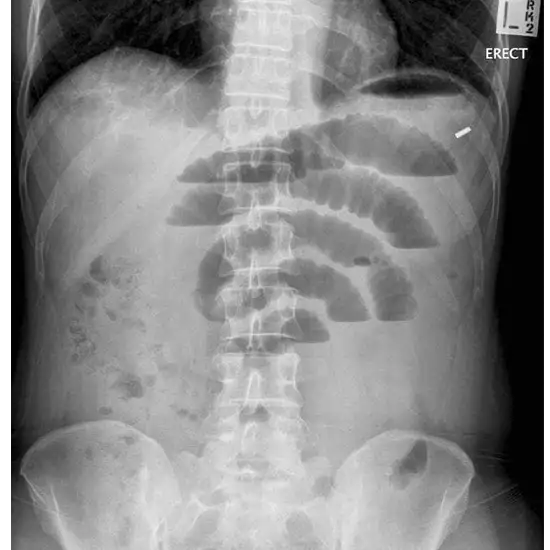

X-Ray Abdomen Erect

When there is a bowel obstruction, X-rays of the abdomen taken while the patient is standing up are used to check for fluid levels.

An X-ray of the stomach may help doctors figure out why someone is having stomach pain or throwing up. It can sometimes find things like kidney stones, a blockage, a hole in the intestines, or a mass like a tumor.

This test is valuable in visualizing gas-fluid levels and free gas in the abdominal cavity. It allows the assessment of ulcers, perforations, intra-abdominal masses, bowel obstructions, or postoperative pain.